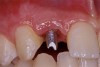

Periapical radiographs were taken to help determine the mesial-distal inclinations of the adjacent tooth roots (Figure 1). The radiographs revealed a serious issue, convergent roots for the right canine and right central, which eliminated that area as a potential implant-receptor site. The space between the left central and canine teeth was minimal, although the roots were relatively parallel. Clinical examination (manual palpation of the root eminences superiorly to the vestibule on the right side) confirmed the root convergence (Figure 2A). The flat, wide zone of the keratinized tissue and lack of interdental papilla was evident for the missing right lateral incisor. There was a marked difference in clinical appearance for the left lateral, which could impact the eventual plan of treatment (Figure 2B). Other significant clinical findings included bilateral facial bone concavities, which existed as a result of the congenitally missing tooth roots. As a diagnostic cue to the underlying bone topography, it is important to follow the demarcation between attached and unattached gingival tissue, and note the crestal width of the available keratinized tissue (Figure 2C).

Figure 2b  Pretreatment buccal views showed (A) root convergence, (B) a difference in clinical appearance of the left lateral, and (C) significant crestal width of keratinized tissue.

Figure 2b

Figure 2c  Pretreatment buccal views showed (A) root convergence, (B) a difference in clinical appearance of the left lateral, and (C) significant crestal width of keratinized tissue.

Figure 2c